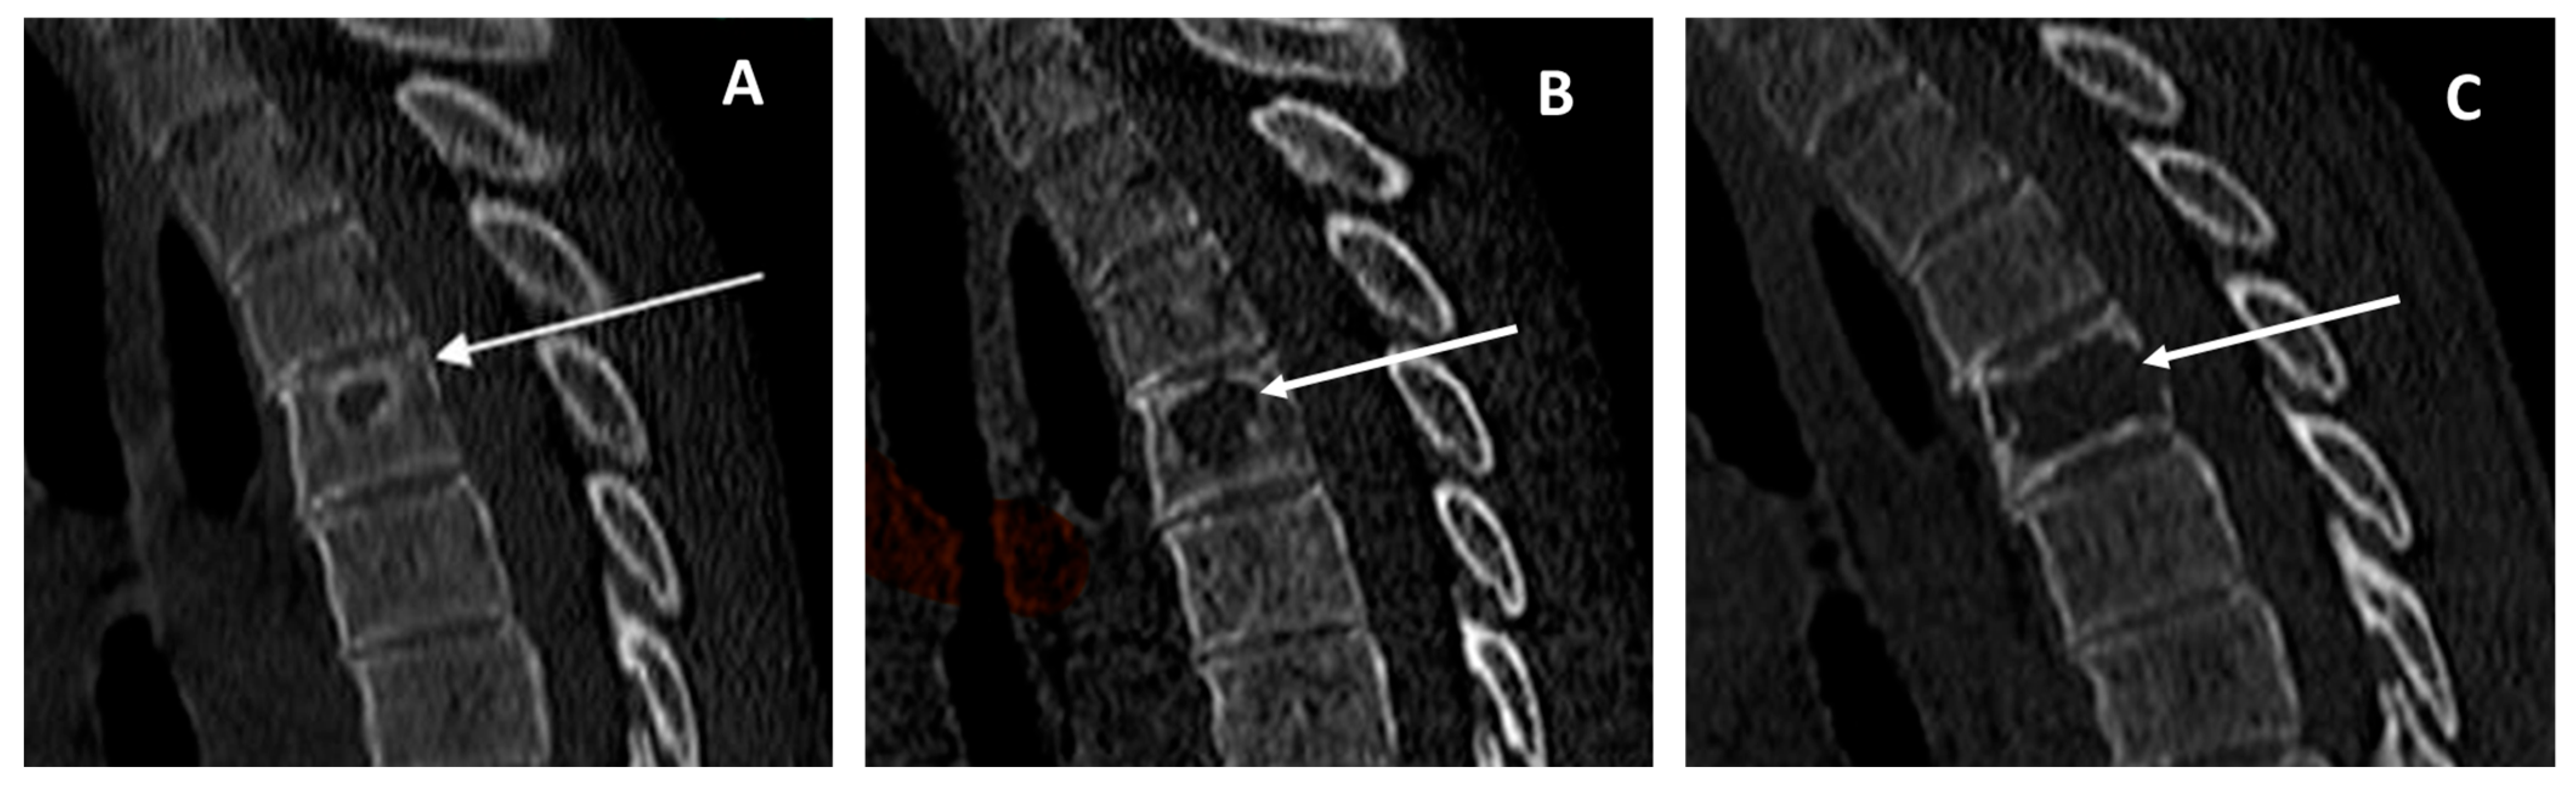

- CT studies were performed on different equipment and completed with bi-dimensional reconstruction (sagittal, coronal). Post-contrast scans were not consistently performed.

- Skip lesions (present/absent, number, and site).

- Lesion main internal pattern (lytic, sclerotic, or mixed).